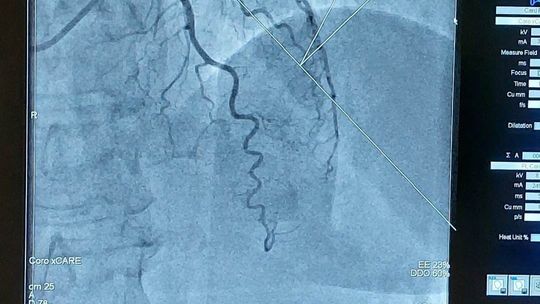

W wizycie udział wzięli: Julia Szukalska, Magda Grela i Kuba Różański oraz dyrektor szkoły Katarzyna Arciszewska-Stępień. Wyjazd był nagrodą w konkursie "Serce na dłoni" organizowanym na początku marca. Po przyjeździe uczniowie przebrali się w medyczną odzież i rozpoczęli obchód po oddziale kardiologii inwazyjnej z ordynatorem dr Januszem Prokopczukiem. Rozmawiając z personelem dowiedzieli się, jak wygląda dzień w klinice. Uczniowie mogli zobaczyć, jak przebiega zabieg wszczepienia rozrusznika serca, koronarografia, elektrokardiografia, wkłucie dożylne i przezprzełykowe echo serca. Nie zabrakło pytań dotyczących studiów na kierunku lekarskim i specyfiki pracy w tym zawodzie. Spotkanie było niesamowicie ciekawe, sprawiło uczniom wiele radości i dodało im motywacji do nauki, by spełnić swoje marzenia o studiach medycznych.

28 marca trójka uczniów II LO im. Mikołaja Kopernika w Kędzierzynie-Koźlu odwiedziła Polsko - Amerykańską Klinikę Serca w Koźlu.